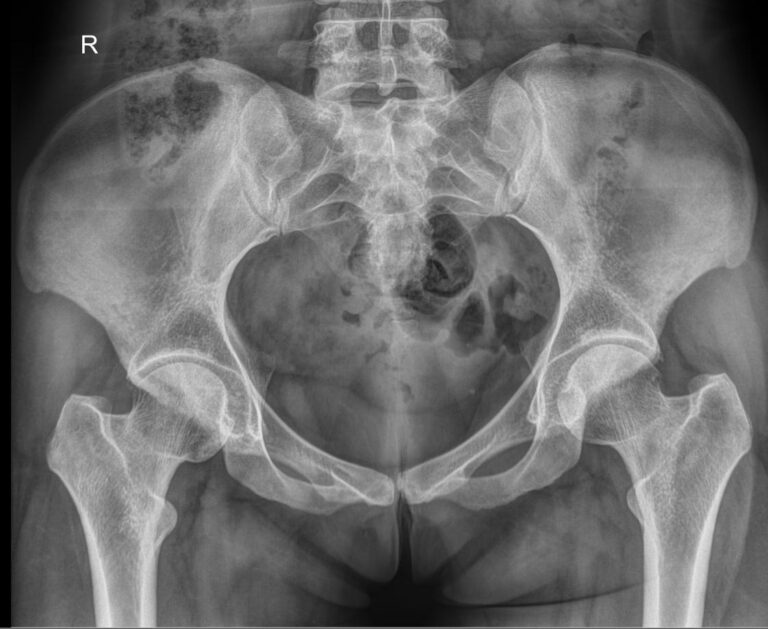

Рентгеновская методика основана на способности ионизирующего излучения проходить сквозь ткани. Кости, как самые плотные образования тела, поглощают наибольшее количество излучения и на негативном снимке визуализируются самыми светлыми. Все изменения ― от трещин до опухолей ― видны четко. Еще один плюс в том, что на рентгенограмме видны сразу все расположенные здесь костные структуры: нижние поясничные позвонки, крестец и копчик, а также тазовые кости ― лонная, седалищная и подвздошная.

Что показывает рентген костей таза

• Костную структуру: есть ли участки разрежения;

• Состояние крестцово-подвздошных сочленений ― в норме должны быть симметричны;

• Переломы, в том числе зажившие;

• Если есть новообразования или метастазы ― указывают их местоположение и размеры.